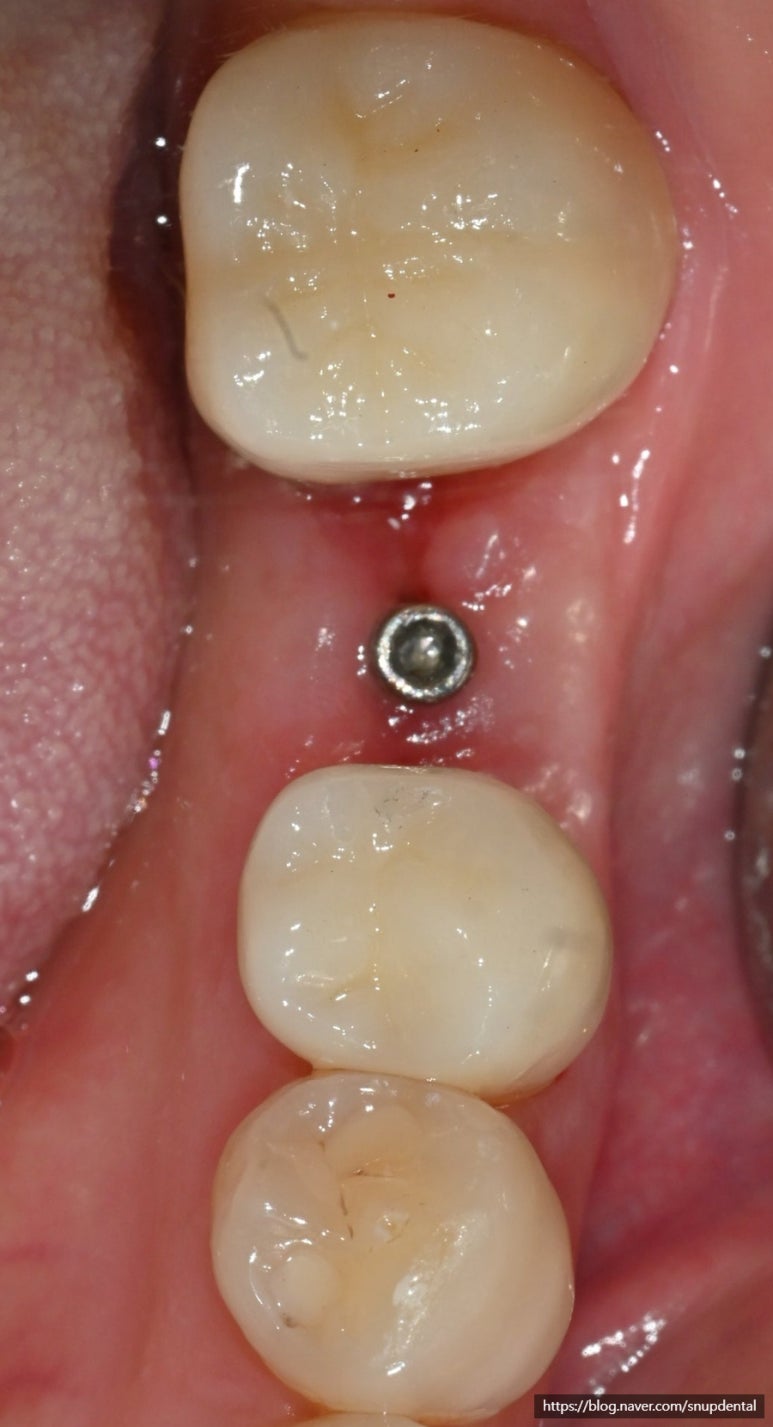

임플란트 수술 후 구강 내 사진 및 부분 CT 캡처 사진입니다

살려 쓰기로 한 작은 어금니 및 근관치료(신경치료) 한 어금니는 임시치아를 사용하면서 불편함이 없음을 확인.

맞춤형 지대주 연결 및 PMMA 임시치아 부착.

임플란트 수술 후 부분 CT 및 구강 내 사진

작은 어금니 및 두 번째 어금니는 지르코니아 최종 수복물을 임시 접착하여 사용 중입니다

THAB를 사용하여 보다 많은 부착치은이 생성될 수 있도록 유도하고 잇몸을 여는 2차 수술을 생략하도록 하였습니다.

임플란트가 골 유착이 되는 2-3개월 후 맞춤형 지대주 및 보철 진행 예정입니다.